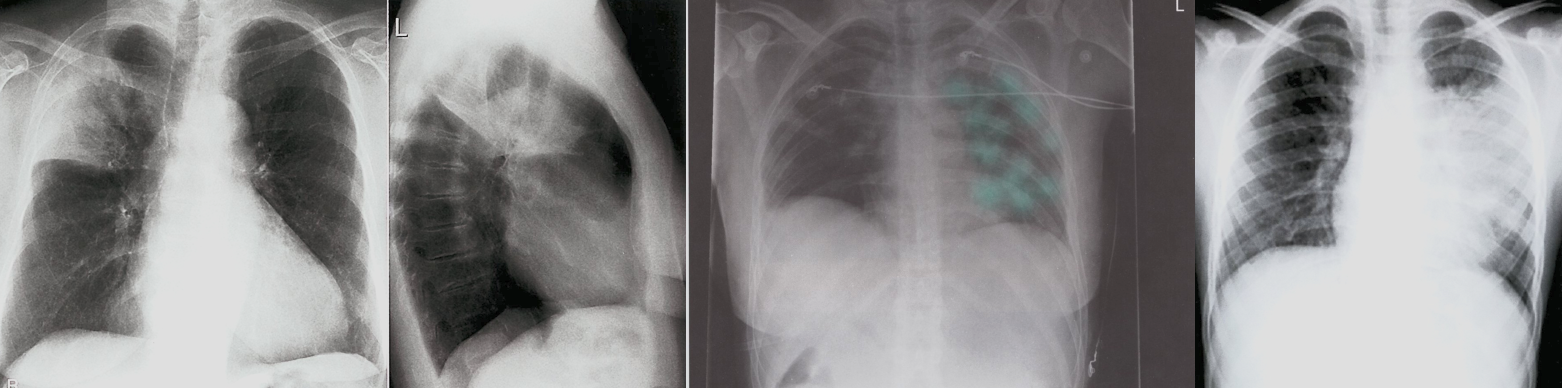

- Acute, Antero (CC)

What will you do next? ECG

What is your diagnosis Acute Anteroseptal myocardial infarction

IF EXG looks like this what is your diagnosis? Acute Inferior MI

CASE SCENERIO 2

30 yo m with history of ankle f 2 weeks ago, c/o sudden onster of chest pain

- ECG; sinus tachycardia, S1 Q3 T3

- Chest x-ray (West hamptom palla signs) - CT

What will you do next? ECG. X-RAY. CT.

What is your diagnosis Acute Pulmonary Embolism

Pulmonary Angiography (GOLD STANDARD)

•Arrow indicates abrupt termination of a pulmonary artery.